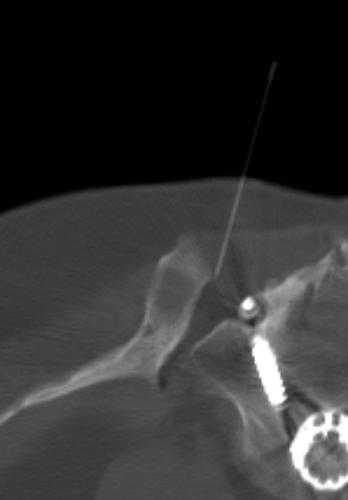

Aufgrund der hohen Präzision moderner bildgebender Verfahren können diese zur gezielten Schmerzausschaltung genutzt werden, wenn der genaue Entstehungsort der Schmerzen bekannt ist. Dies ist beispielsweise häufig bei Wirbelsäulen- und Gelenkerkrankungen der Fall. Dabei wird eine Nadel bildgesteuert an den Schmerzpunkt herangeführt und dort vor Ort entzündungshemmende und analgetische (schmerzausschaltende) Medikamente zielgenau abgegeben. Das ist praktisch in allen Lokalisationen des Körpers (z.B. Tumorschmerzen) möglich. Entscheidend ist eine genaue Diagnostik im Vorfeld, um die Schmerzquelle genau lokalisieren zu können. Wir führen diese Verfahren in Kooperation mit den Schmerztherapeuten unseres Hauses durch. In Zusammenhang mit der Behandlung ist in der Regel eine Physiotherapie sinnvoll.

- Periradikuläre Therapie: Bei diesem Verfahren werden an der Wirbelsäule gereizte Nervenwurzeln behandelt.

- Facettenblockade und Infiltration des Iliosakralgelenkes: Sind Gelenke degenerativ verändert (abgenutzt) und wackelinstabil, so könne sie Entstehungsort von Rückenschmerzen sein. Auch in diesem Fall kann unter Bildsteuerung eine Nadel zielgerichtet an den Schmerzpunkt herangeführt um diesen auszuschalten.